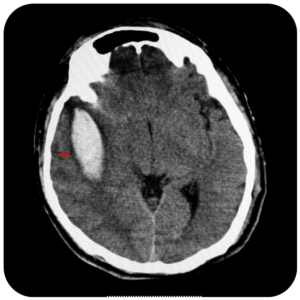

Es un defecto congénito en el cual los huesos de la columna no se forman totalmente, esto provoca un conducto raquídeo incompleto en el cual la médula y las meninges sobresalen de la espalda del niño.

Se corrige mediante un procedimiento quirúrgico llamado meningoplastia, que es el cierre quirúrgico del defecto.